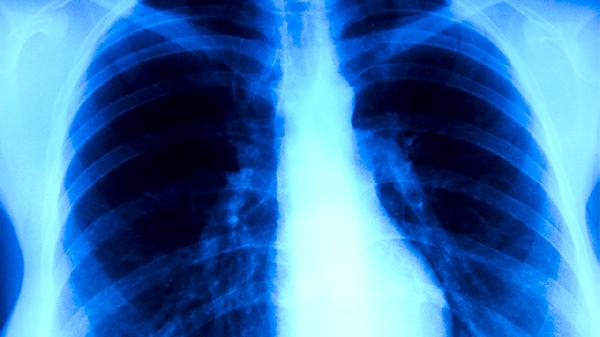

存在EGFR、KRAS等基因突变的个体对致癌物更敏感,家族中有肺癌病史者患病风险增加2-3倍。这类人群应避免吸烟等危险因素,40岁后建议每年进行胸部CT检查。某些遗传性疾病如李-佛美尼综合征也会显著提升肺癌易感性。

预防肺癌需采取综合措施,包括彻底戒烟、使用抽油烟机减少厨房油烟吸入、职业防护佩戴N95口罩、雾霾天减少外出等。建议高危人群每年进行低剂量螺旋CT筛查,出现持续咳嗽、痰中带血、胸痛等症状时应及时就诊。保持膳食富含维生素A/C和硒等抗氧化营养素,规律运动增强免疫功能也有助于降低风险。